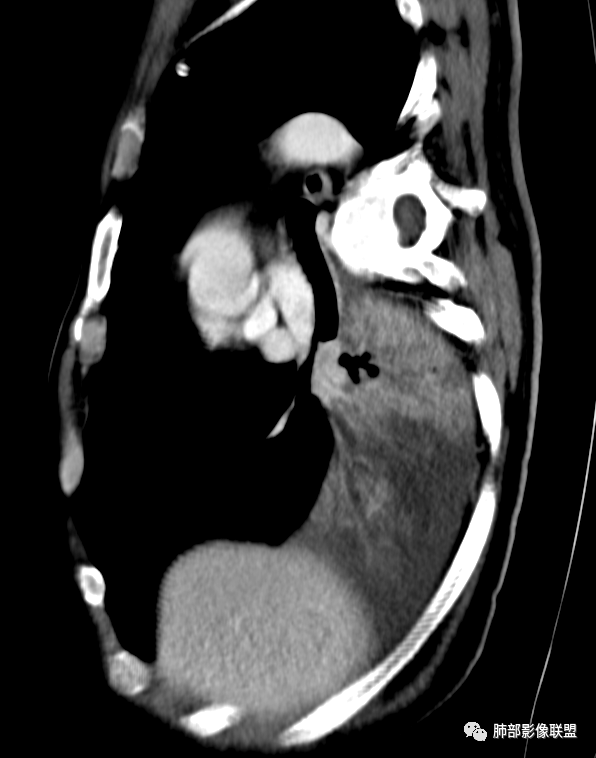

冠状位重建有钻缝的感觉

南边:

粘液腺不符合

粘液腺是外围朝内推移的

不应该近端腔内结节强化明显

我再发一些图

这是源头

这些如果单纯不张肯定强化明显